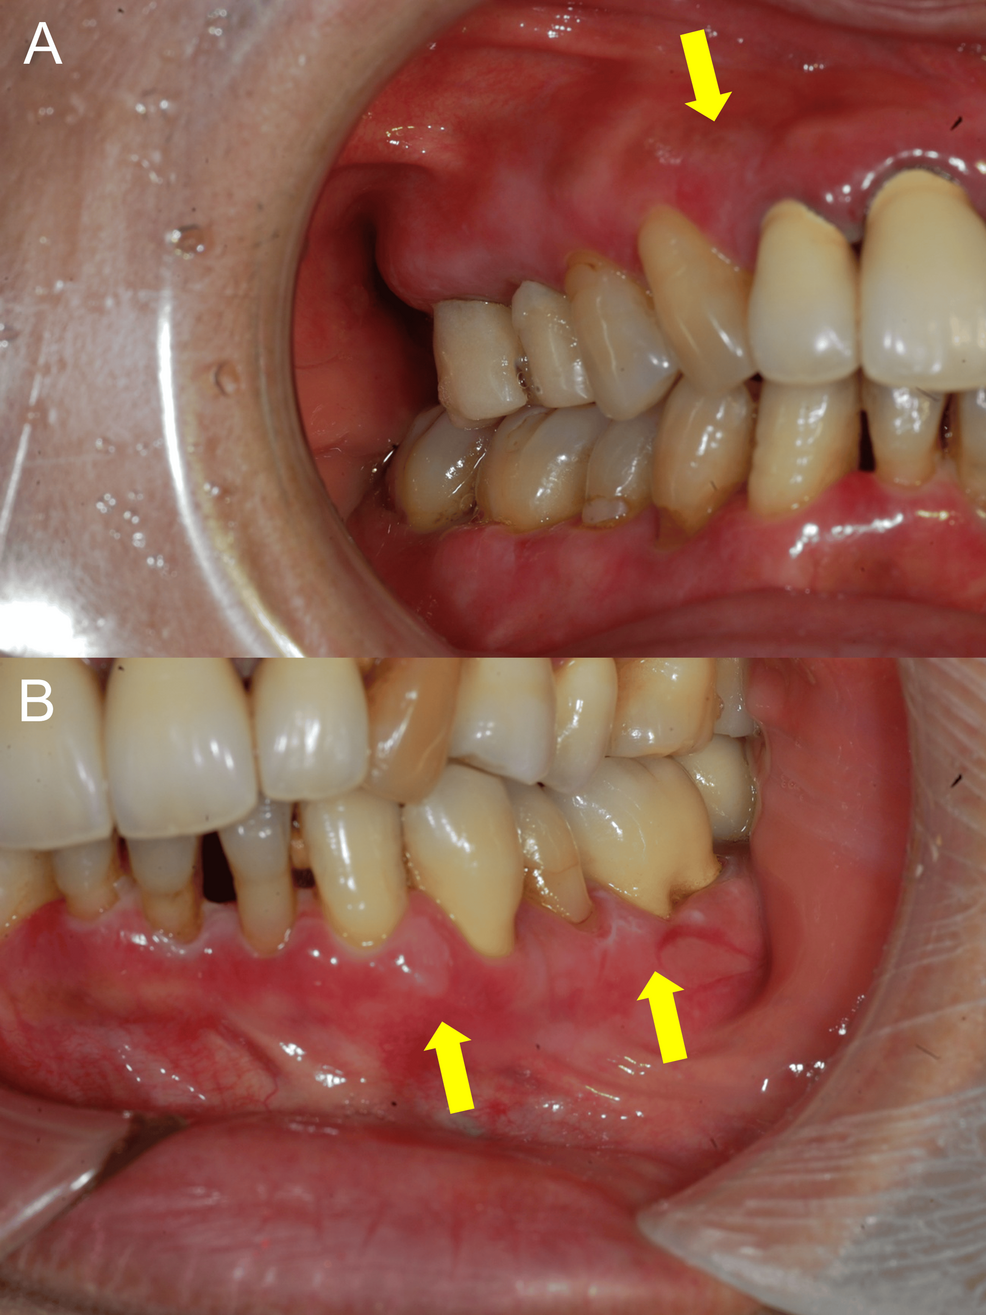

The typical clinical features of bullous pemphigoid include itchy, blistering skin, often starting on the limbs and trunk. However, the gingival-dominant presentation, as observed in recent case reports, presents a diagnostic challenge. In these cases, the initial and sometimes sole manifestation of BP is blistering and ulceration of the gums. This can mimic other oral conditions, such as lichen planus or mucous membrane pemphigoid, leading to delays in accurate diagnosis. A 2019 article in Frontiers in Immunology details the complexities of DPP-4 inhibitor-associated bullous pemphigoid, emphasizing the need for heightened awareness among dermatologists and oral health professionals [2].

Diagnosing gingival-dominant BP requires a high index of suspicion, particularly in patients with type 2 diabetes taking DPP-4 inhibitors. The diagnostic process typically involves a skin biopsy to examine for characteristic immune deposits, as well as blood tests to detect BP autoantibodies. However, it’s key to note that autoantibody testing may not always be positive, especially in the early stages of the disease or in cases with atypical presentations.

Treatment for DPP-4 inhibitor-associated BP generally involves discontinuing the suspected medication and initiating systemic corticosteroids, which suppress the immune system and reduce inflammation. In some cases, other immunosuppressant medications, such as mycophenolate mofetil or azathioprine, may be used as steroid-sparing agents. A study published in Diabetes Care in 2019 highlighted the uncertainties surrounding the association between DPP-4 inhibitors and bullous pemphigoid, calling for further research to establish definitive guidelines for management [3]. A case report published in ScienceDirect in 2023 details a patient with type 2 diabetes taking DPP-4 inhibitors who developed blisters on her gums, further illustrating the potential for oral manifestations [4].